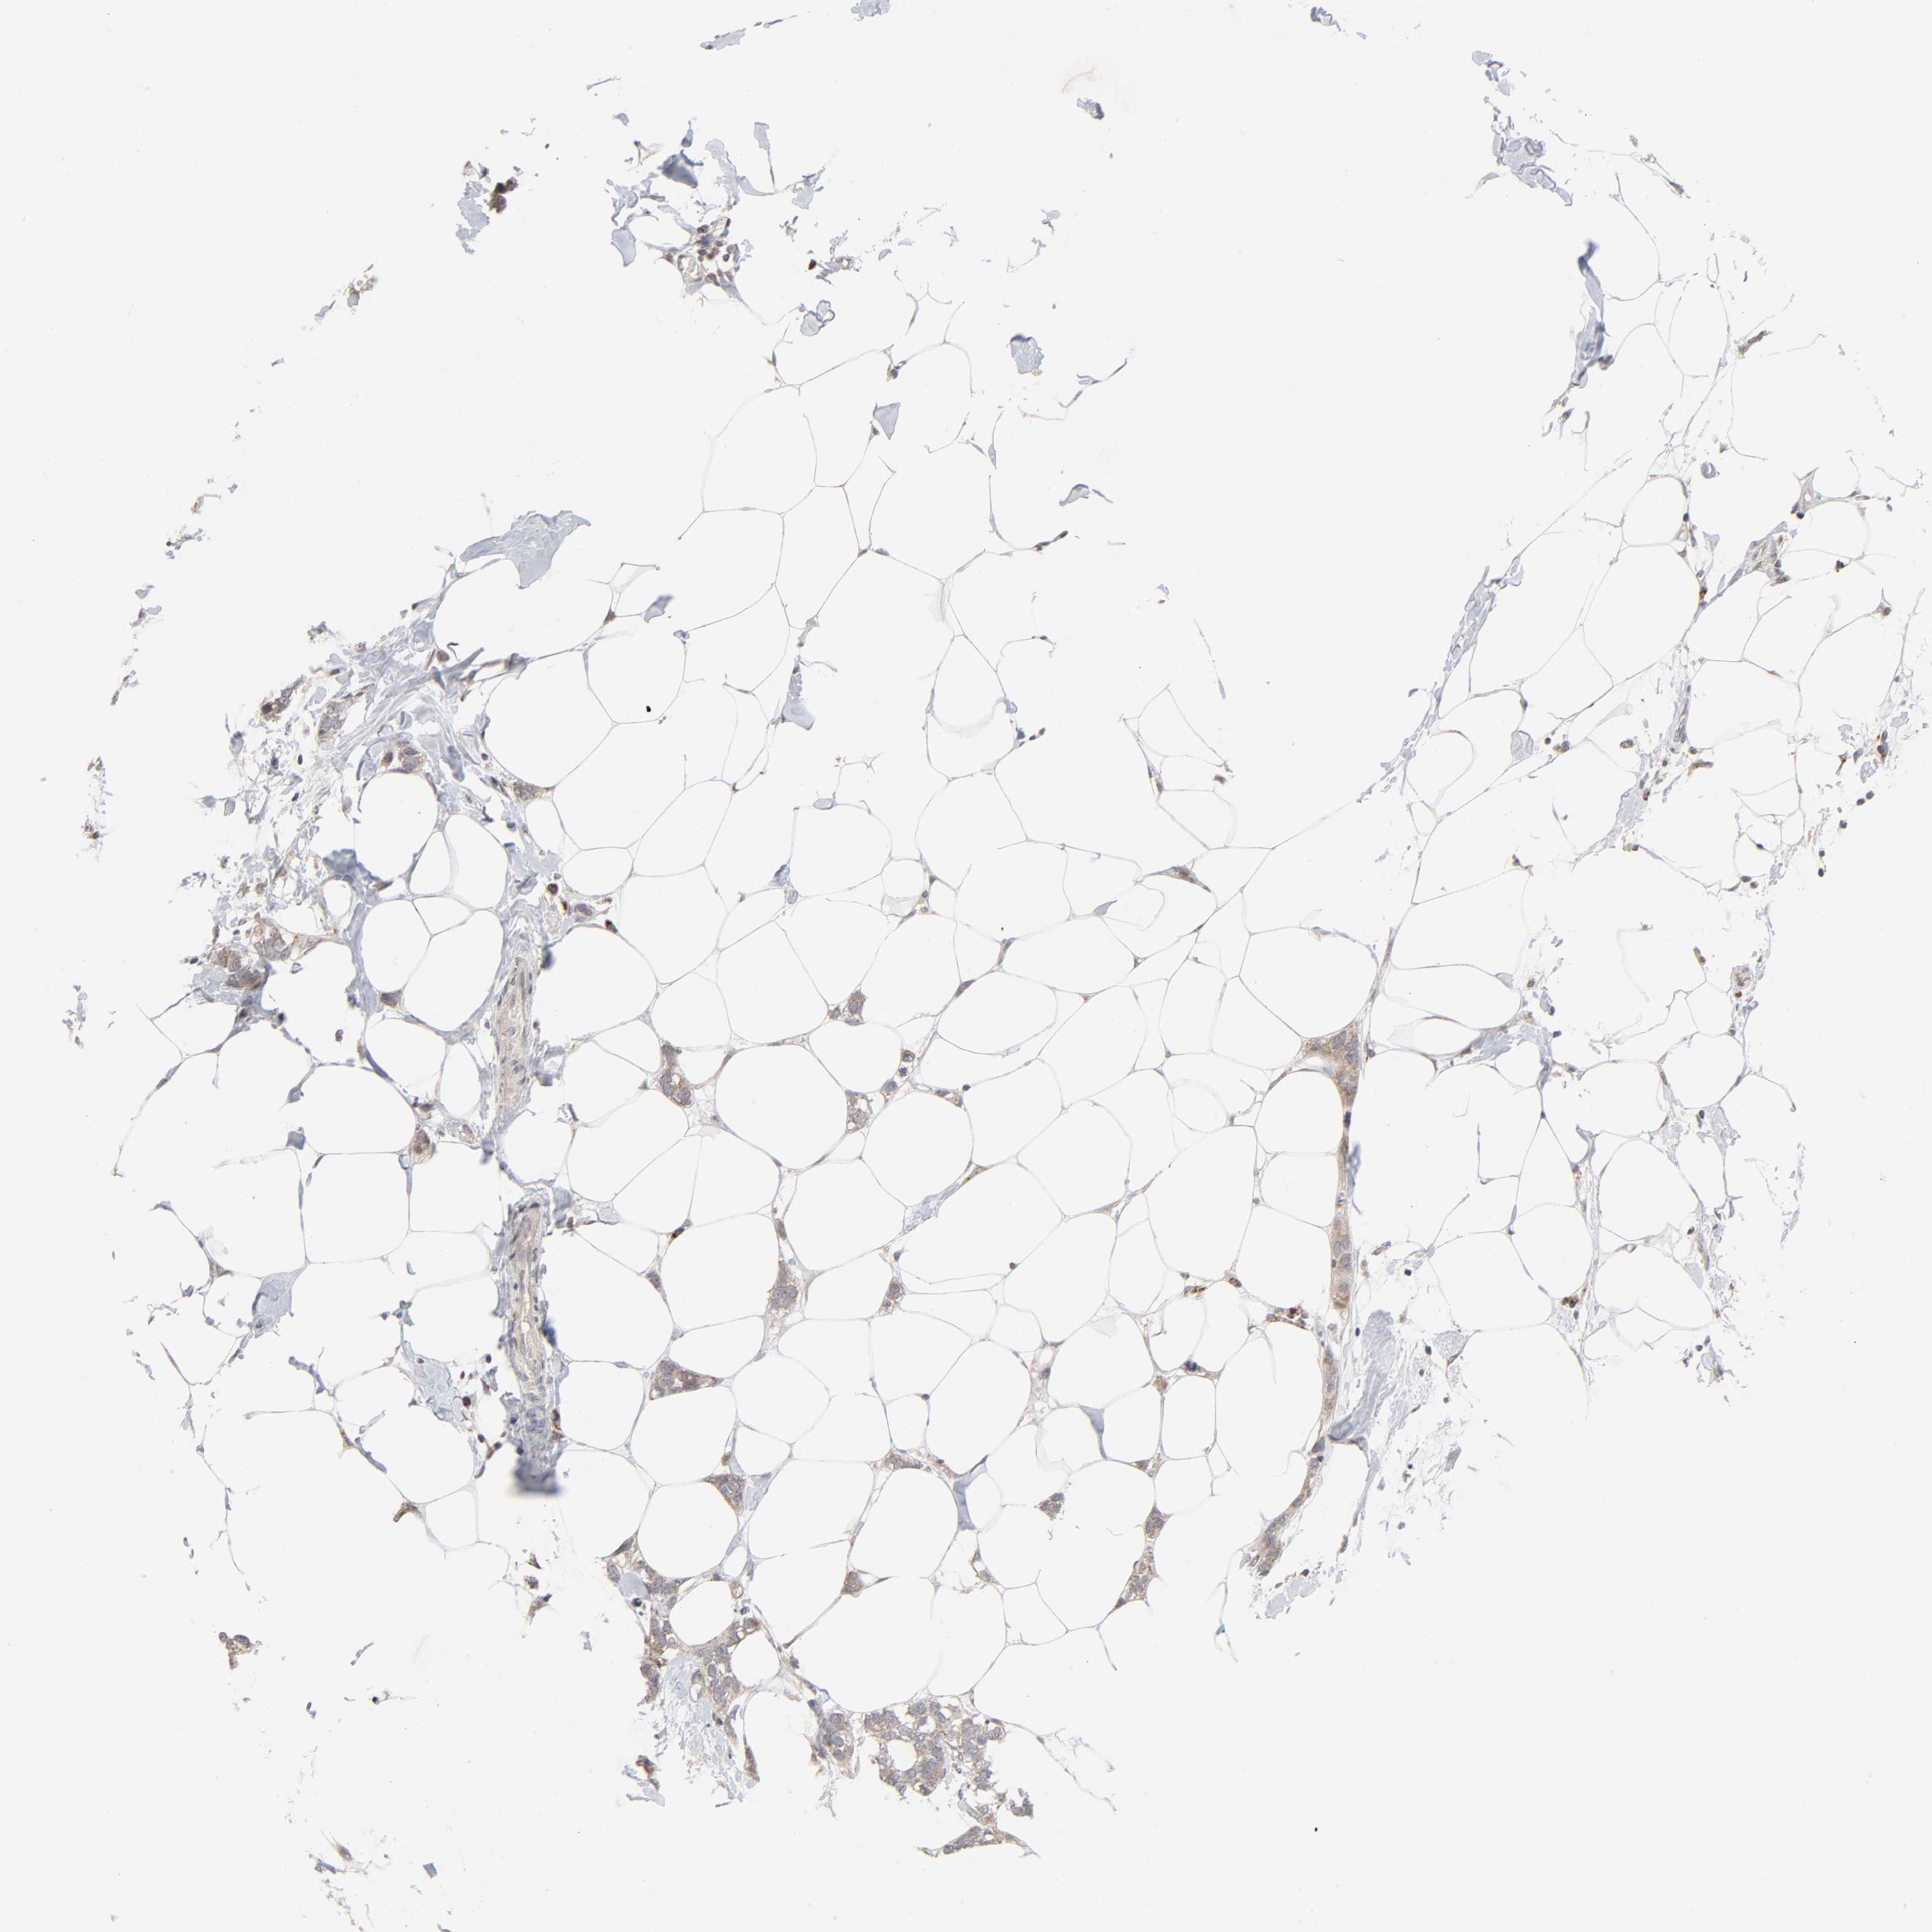

CANCER BREAST CANCER Show tissue menu

BRCA TCGA BRCA VALIDATION PROTEIN EXPRESSION